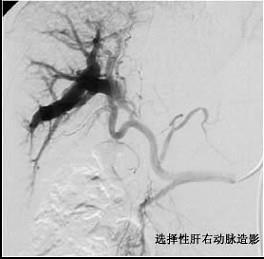

问题 诊断直径小于2cm的肝癌,最好的定位方法是 ( )

选项 A、胆道造影术 B、选择性腹腔动脉造影术 C、同位素肝扫描 D、B型超声波检查 E、肝穿刺术

答案 B